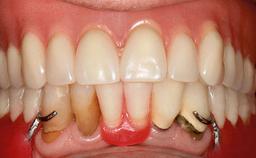

Early (Type 2) placement in a healthy, non-smoking male patient aged 28 years who required removal and replacement of the maxillary right central incisor due to external root resorption. A horizontal bone deficit requires a simultaneous augmentation procedure. The overall esthetic risk is high due to the horizontal bone deficit, medium to high lip line with exposure of the soft tissue margin when smiling, and the patient’s high esthetic expectations.

After flapless tooth extraction and a healing period of 6 weeks, a standard-diameter one-piece implant is placed. A gap between the implant and the facial bone wall is filled with autogenous bone chips harvested from the anterior nasal spine and covered with DBBM particles. Contour augmentation on the facial aspect is achieved using DBBM particles and a collagen membrane, according to the principles of guided bone regeneration (GBR). The flap is coronally repositioned for semisubmerged healing.